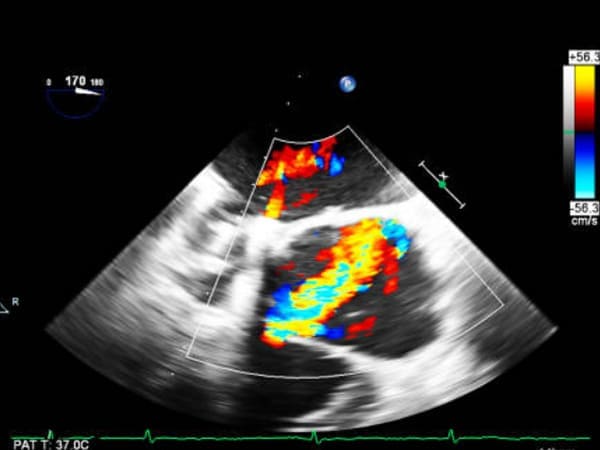

Ecocardiograma estrés

Si eres un practicante de deportes quizá deberías de tomar la opción de realizar un ecocardiograma de estrés con este ultrasonido podrás conocer las características de tu ritmo cardiaco. Ven al consultorio a conocer tu estado cardiaco.

Ecocardiograma que utiliza la infusión de fármacos intravenosos para evaluar de forma completa la respuesta del corazón a estos estímulos....